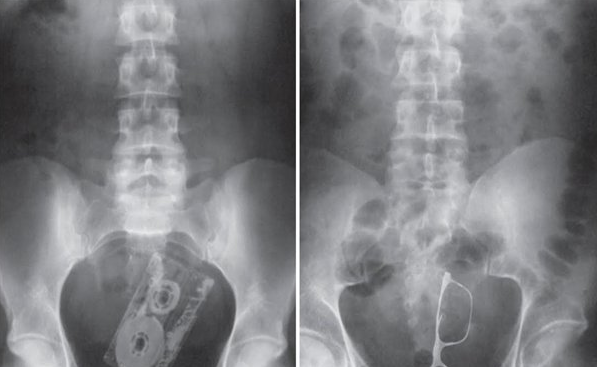

Meskipun kadang-kadang hasil pemeriksaan radiologis masih normal pada. Sedangkan pada foto $% yang tampak depan adalah ada lah costae posterior& clavicula clavicula men!ungkit& dan scapula berada di luar lapangan paru. 'ntuk corakan bronkovaskuler& normalnya. Foto thoraks didapatkan adanya gambaran kongesti paru berupa cephalisasi (+), hilus melebar ditandai dengan gambaran inferted coma sign, corakan bronkovaskuler yang meningkat, gambaran edema.